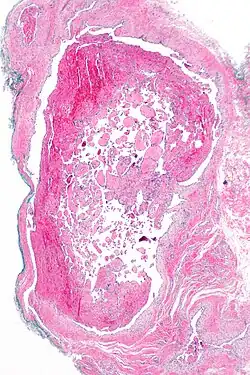

| Micrograph of intravascular papillary endothelial hyperplasia. H&E stain. | |

Immunohistochemistry staining in addition to a thorough histomorphological evaluation are necessary for a correct diagnosis.[10] A crucial tool for diagnosing it is microscopy. IPEH is made up of an intravascular proliferation of many papillae with an endothelial surface and a connective tissue core.[11] It differs from other neoplastic lesions in that it is often encapsulated or well-circumscribed, displaying distinctive papillary fronds, and the vascular wall completely restricts the proliferative process.[12]